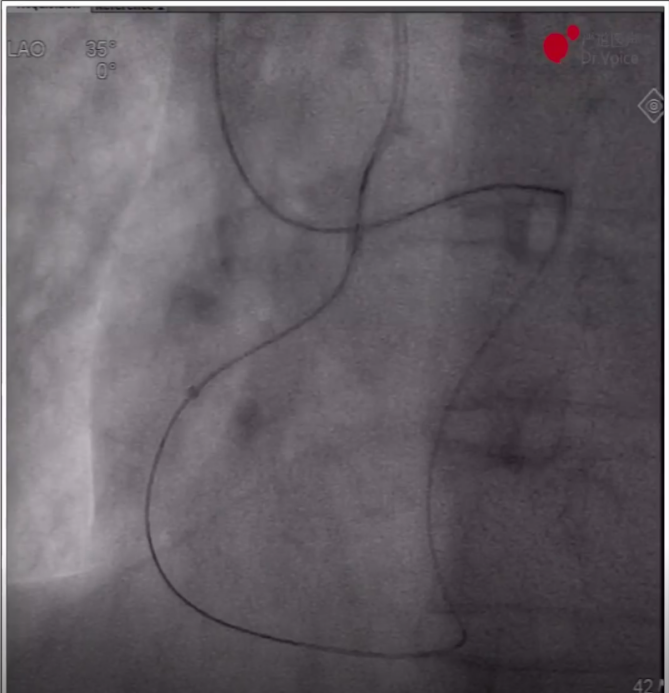

7、重新送入导管后,调整正向和逆向导丝重叠,通过AGT技术将逆向导丝送入正向指引导管,正向球囊锚定逆向导丝后,跟进逆向corsair150微导管至正向指引导管,正向runthrough导丝穿逆向微导管后完成轨道建立。

逆向导丝进入正向导管内